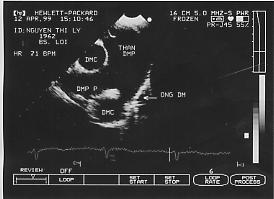

1. Hình ảnh trực tiếp của ống động mạch trên siêu âm 2D thấy đợc ở mặt cắt trên ức và qua các gốc động mạch lớn. Đo đường kính và đánh giá hình thái của ống. Siêu âm Doppler mầu xác định chính xác vị trí đổ vào ĐMP của ống động mạch.

Hình 29-2. Dòng chảy qua ống động mạch trên siêu âm Doppler mầu.